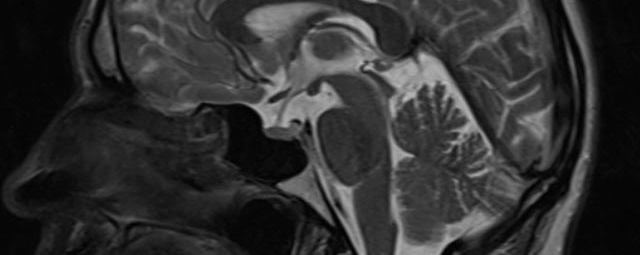

- Multiple Sklerose

- Diffusionswichtung

- Perfusionswichtung

- Suszeptibilitätswichtung

- MR-Spektroskopie

Diese Verfahren werden bei verschiedenen Fragestellungen in verschiedenen Körperregionen in die Messprotokolle sinnvoll eingefügt. Teilweise können dadurch Differenzierungenverschiedener krankhafter Prozesse verbessert werden.